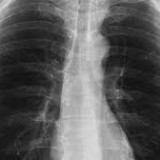

Untuk menemukan masyarakat yang terkena TBC (tuberkulosis), Dinas Kesehatan (Dinkes) Tulungagung menyediakan fasilitas pemeriksaan dahak secara gratis. Fasilitas ini diperuntukan bagi masyarakat yang mempunyai gejala TBC, seperti batuk yang tidak sembuh-sembuh dan berdahak.

Untuk mengecek dahak, Dinkes Tulungagung menggunakan dua alat tes cepat molekular (TCM yang diklaim lebih sensitif dibanding mikroskop. Satu mesin ada di Puskesmas Ngunut dan satu mesin di RSUD dr Iskak.